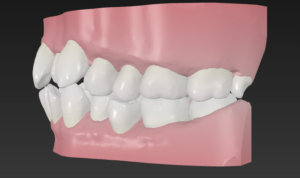

🔶初診時🔶

正面

右

左

歯並びガタガタの そうせい を気にして

マウスピース矯正希望で来院